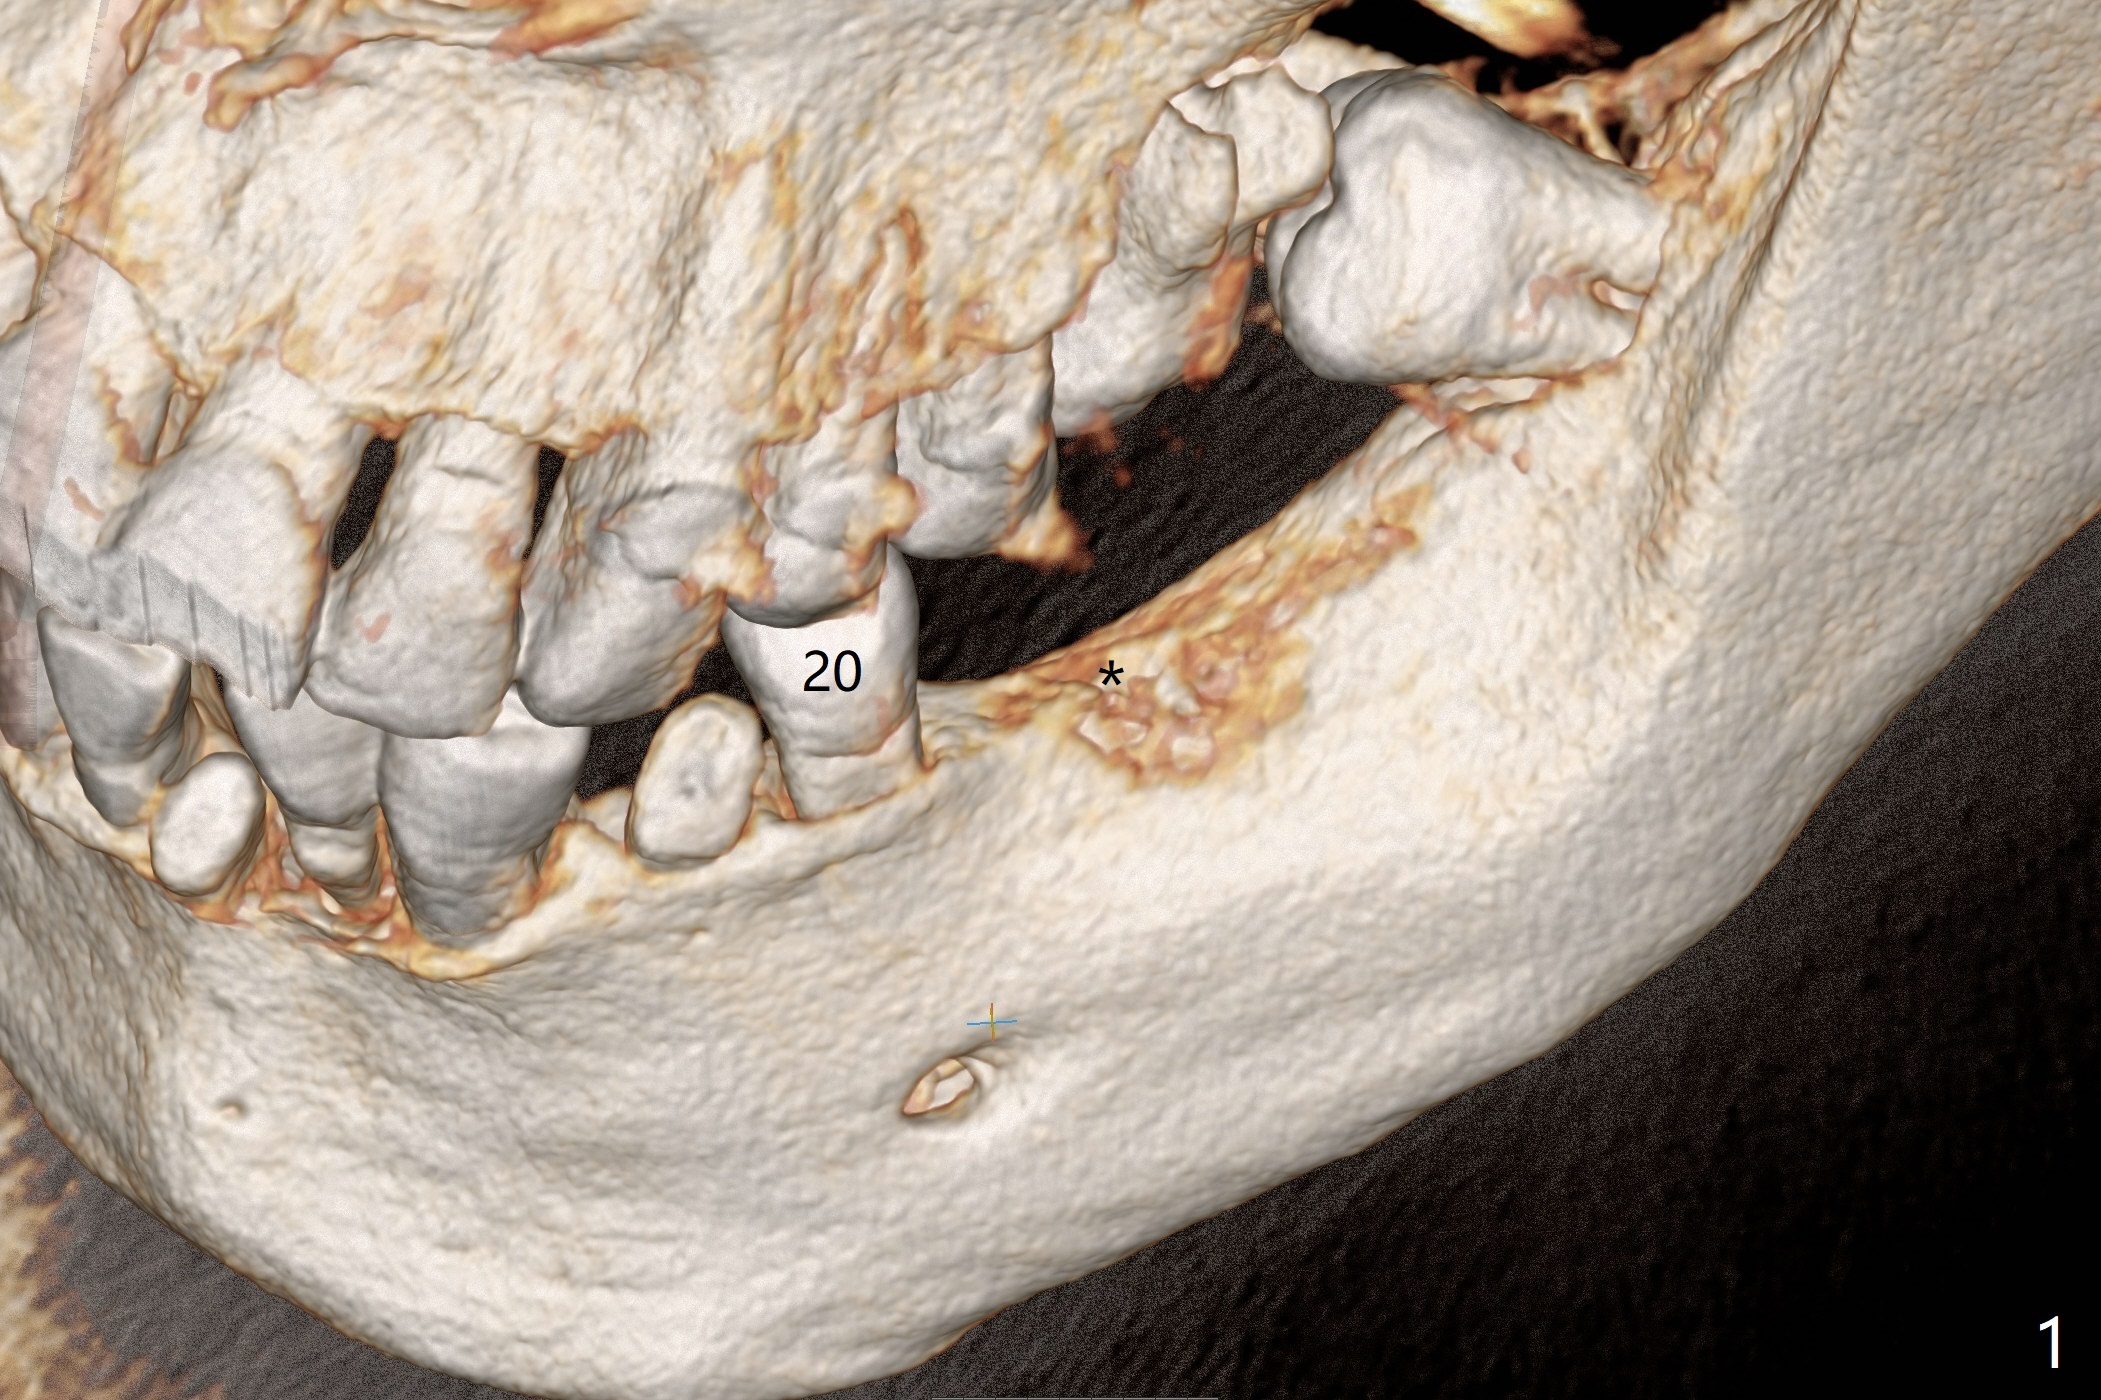

A 54-year-old man has poor dentition, including missing tooth of #19 and residual root at #20 (Fig.1). The lingual crest (Fig.2 (lingual view), Fig.4 (L)) is lower than the buccal one. The Inferior Alveolar Canal (Fig.3 IAC) becomes the Incisive Canal (IC, Fig.4 red circle) after the Mental Loop (Foramen). An implant at #21 will be placed at the level between the buccal and lingual crests (Fig.4) with osteotomy initiated in the middle of the socket. Bone graft is to be placed around the coronal end of the implant (yellow circles).

The socket at #19 appears to have not completely ossified (Fig.1 *, Fig.5). Use Magic Split and Magic Expanders to expand the ridge top so that an implant will be placed higher for favorable crown/implant ratio (reduce abutment screw loosening). Note the concavity at the site of #19 while osteotomy (Fig.2 *).